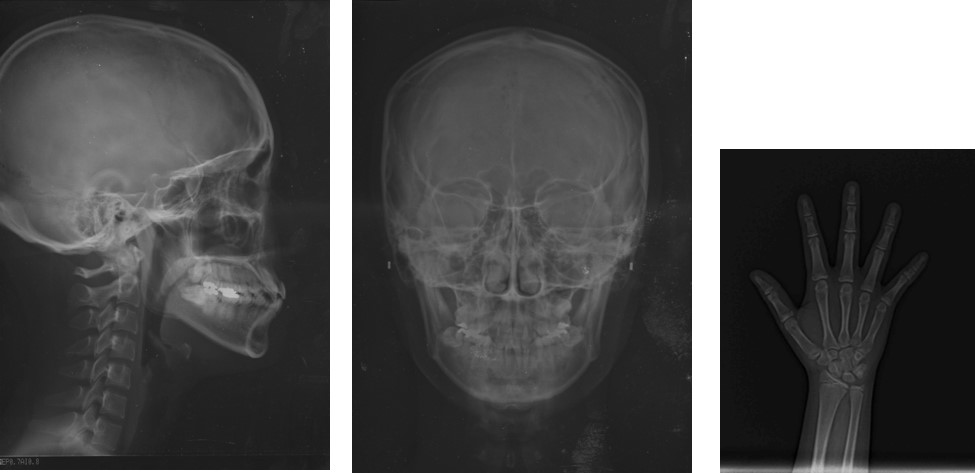

手の骨は、年齢によって成長の度合いがほぼ決まっているため、手の骨の形や数を調べることで、 全身の骨の成長段階を知ることができます。 実年齢と骨年齢を比べることで、骨の成長が遅いか早いかを判断できます。 こったんせん しゅこんぶ図2小児の大腿骨遠位部(膝の部分)のレントゲン像。 左が正常で、右は骨折した骨です。 左の矢印の黒く抜けた線は、骨端線とよばれ、成長してゆく軟骨の部分で、レントゲンに写りません。 右の矢印は、骨端線での骨折を示します。MCPs, 指, 手関節 –Soft tissues軟部組織の腫脹や石灰化 –Bones 骨の密度は正常か?

橈骨遠位骨端線損傷(SalterHarrisのⅡ型)が認められました。 転位が認められたため、徒手整復を行い、ギプスによる固定を行いました。 左の写真は、徒手整復を行い、ギプス固定をした状態でのレントゲンです。 赤色矢印で示したように、 転位した骨子どもの心臓病は、大きく分けて三つのタイプがあります。 小児心臓の専門医のいる病院に通院し、心電図、胸部レントゲン、心エコーなどの検査を受けましょう。 ミルクは一回の量をやや少ない目にし、こまめにあげるのも一つの手でしょう。手と手首のx線像で注目にあたいする 規則的に,明確にそして不可逆的な順序で現れる個々の 骨の特徴的な骨化様相を骨成熟指標という(12)。色々 な骨成熟の評価法があるが,それらは基本的には似てい る。ある子どもの手と手首のレントゲン写真を一連

他に手のレントゲンで予測を行ったりします。 これは幼児(私の下の娘)の手のレントゲンです。 小さな子供では手の付け根の骨の数は少ないです。 この状態からどんどん成長すると、このようなレントゲンになります。